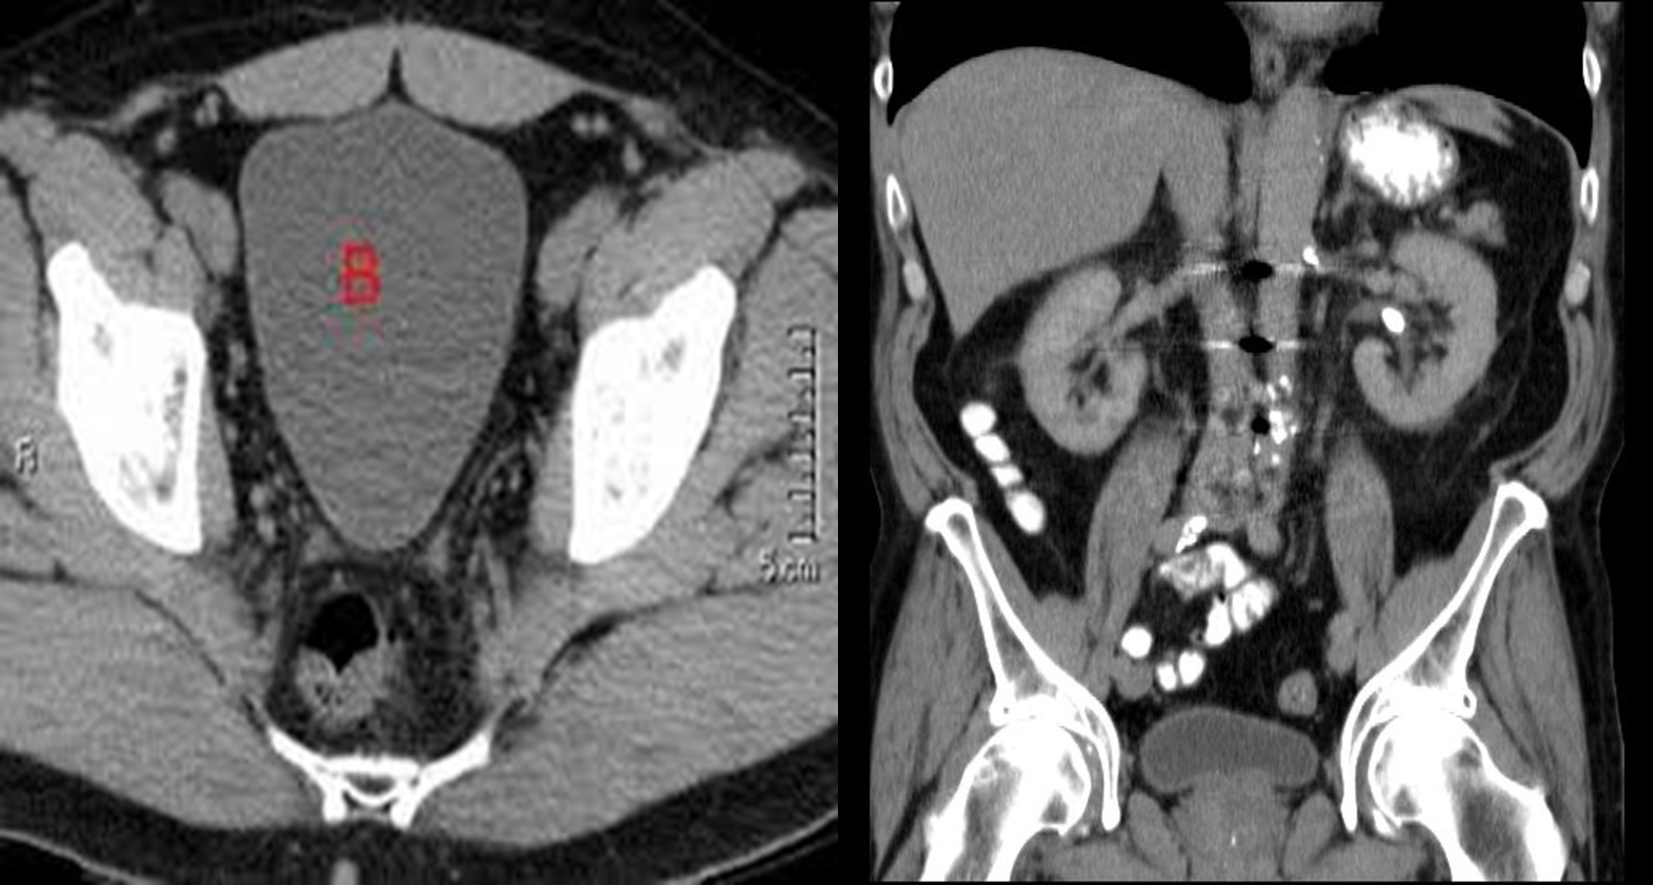

Standard CT technique for renal imaging:

IV contrast differentiate pathological process from normal.

Computed tomography of kidneys, ureters and bladder (CT KUB) is a quick non-invasive technique for diagnosis of urolithiasis

CT urography (CTU or CT-IVU) has now largely replaced traditional IVU in imaging the genitourinary tract. It gives both anatomical and functional information.